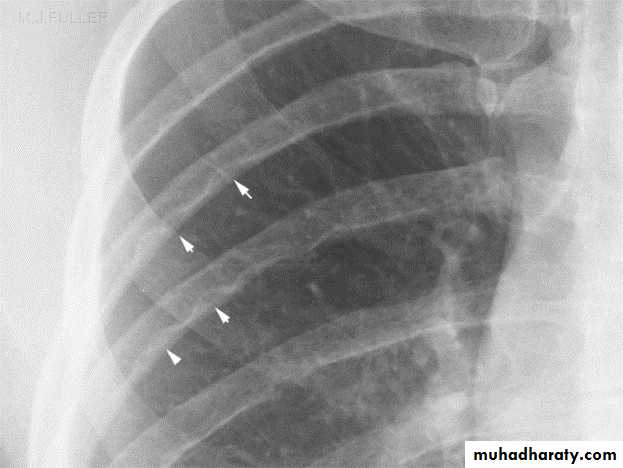

In older children(>8 years) the chest x-ray film may show notching

of the ribs due to the development of collaterals.